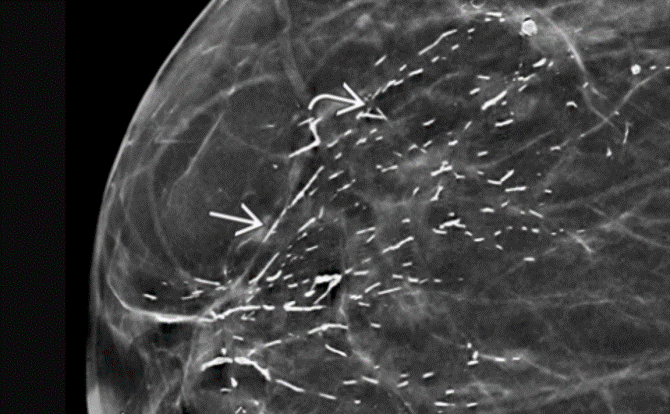

dermal calcs

dermal calcs:

most common in the parasternal area and inframammary fold